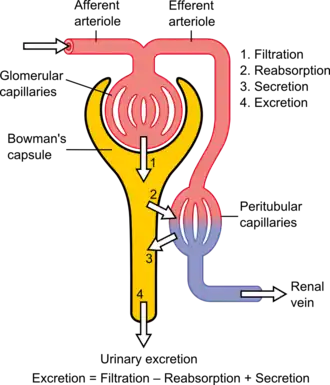

Pathophysiologic abnormalities in diabetic nephropathy usually begin with long-standing poorly controlled blood glucose levels. This is followed by multiple changes in the filtration units of the kidneys, the nephrons. (There are normally about 750,000–1.5 million nephrons in each adult kidney).[8] Initially, there is constriction of the efferent arterioles and dilation of afferent arterioles, with resulting glomerular capillary hypertension and hyperfiltration particularly as nephrons become obsolescent and the adaption of hyperfiltration paradoxically causes further shear stress related damage to the delicate glomerular capillaries, further proteinuria, rising blood pressure and a vicious circle of additional nephron damage and decline in overall renal function.[9][10] Concurrently, there are changes within the glomerulus itself: these include a thickening of the basement membrane, a widening of the slit membranes of the podocytes, an increase in the number of mesangial cells, and an increase in mesangial matrix. This matrix invades the glomerular capillaries and produces deposits called Kimmelstiel-Wilson nodules. The mesangial cells and matrix can progressively expand and consume the entire glomerulus, shutting off filtration.[11]

The status of diabetic nephropathy may be monitored by measuring two values: the amount of protein in the urine - proteinuria; and a blood test called the serum creatinine. The amount of the proteinuria reflects the degree of damage to any still-functioning glomeruli. The value of the serum creatinine can be used to calculate the estimated glomerular filtration rate (eGFR), which reflects the percentage of glomeruli which are no longer filtering the blood. Treatment with an angiotensin converting enzyme inhibitor or angiotensin receptor blocker, which dilates the arteriole exiting the glomerulus, thus reducing the blood pressure within the glomerular capillaries, may slow (but not stop) progression of the disease. Three classes of diabetes medications – GLP-1 agonists, DPP-4 inhibitors, and SGLT2 inhibitors– are also thought to slow the progression of diabetic nephropathy.[12]

The disease progression of diabetic nephropathy involves various clinical stages: hyperfiltration, microalbuminuria, macroalbuminuria, nephrotic proteinuria to progressive chronic kidney disease leading to end-stage renal disease (ESRD). The damage is exerted on all compartments of the kidney: the glomerulus, the renal tubules, the vasculature (afferent and efferent renal arterioles) and the interstitium. Renal fibrosis is the final common pathway of DN. This fibrosis is a product of multiple mechanisms including renal hemodynamic changes, glucose metabolism abnormalities associated with oxidative stress as well as inflammatory processes and an overactive renin-angiotensin-aldosterone system (RAAS).

Hemodynamic factors include an increase in systemic and intraglomerular pressure, as well as the over-activation of the RAAS. Studies have shown that in the setting of diabetes, various factors stimulate the RAAS, which is one of the most important pathways in diabetic nephropathy pathophysiology. Due to the higher load of filtered glucose, there is an up-regulation in the sodium-glucose cotransporter 2 (SGLT2) in the proximal tubules, which cotransports sodium and glucose back into circulation. This leads to a decrease in the delivery of sodium chloride to the macula densa in the distal tubules, promoting the release of renin and over-activating RAAS.[22] Hyperfiltration is one of the earliest features of DN. Several mechanisms have been proposed to cause hyperfiltration. One of these mechanisms is that as glomeruli becomes hypertrophied, filtration surface area initially increases. Another possible mechanism is that abnormal vascular control in diabetic nephropathy leads to a reduction in afferent glomerular arteriolar resistance and an increase in efferent glomerular arteriolar resistance, leading to a net increase in renal blood flow (RBF) and glomerular filtration rate (GFR).[23] Glomerular hyperfiltration and an aberrant regulation of RAAS lead to increased intraglomerular pressure, causing stress on the endothelial cells, the mesangial cells and the podocytes. This exacerbates the dysfunction caused by the metabolic effects of hyperglycemia.